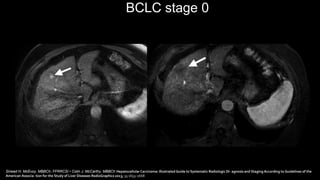

BCLC stage 0

Sinead H. McEvoy, MBBCh, FFRRCSI • Colin J. McCarthy, MBBCh Hepatocellular Carcinoma: Illustrated Guide to Systematic Radiologic Di- agnosis and Staging According to Guidelines of the

American Associa- tion for the Study of Liver Diseases RadioGraphics 2013; 33:1653–1668